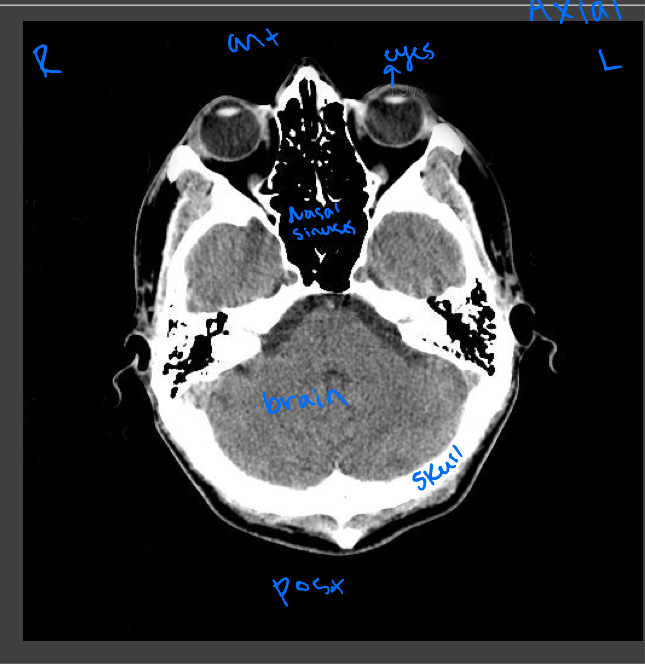

Axial CT images

Presented as if the viewer is standing at the foot of the patient’s bed; the patient’s right is to the viewer’s left; the anterior aspect of the patient is toward the top of the image

Head and neck CT

Evaluating traumatic injury or to rule out bleeding or fracture, intercranial bleeds